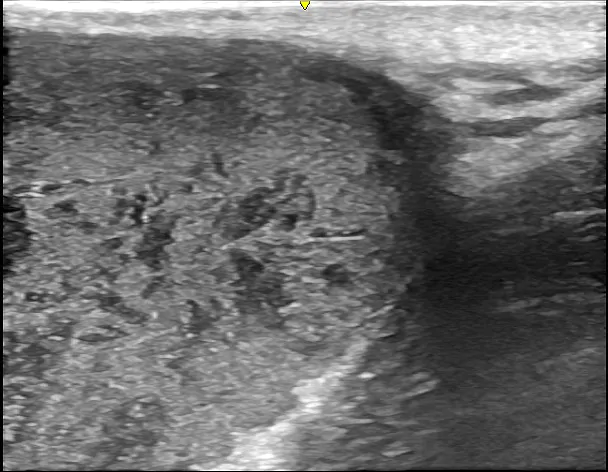

徐々に皮下腫瘍が大きくなったため、当院を受診されました。左肩に120mm大の巨大な皮下腫瘍があり、超音波検査の結果、典型的な粉瘤と診断されました。

術中①切開で角質を排出